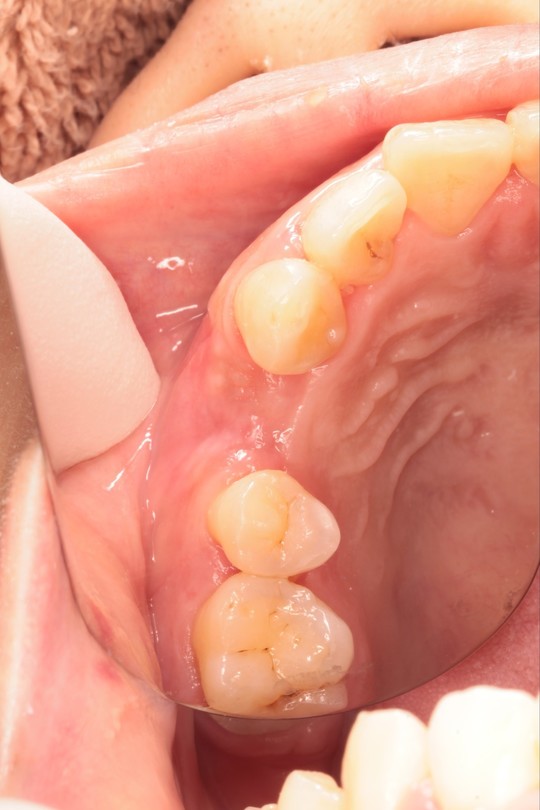

①根が割れた状態

②抜歯同時骨造成